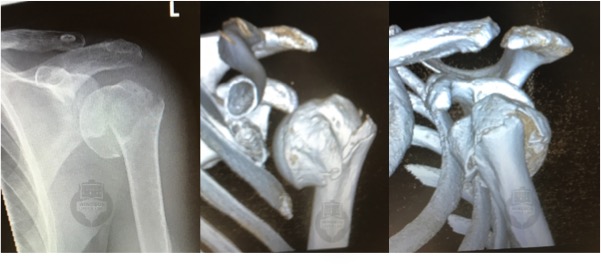

Your history and examination findings will be highly suggestive.  X-rays taken in the Emergency department will confirm the fracture.  Sometimes a CT scan is performed to assess more closely the displacement of the fracture fragments, damage to the articular surface and potential for surgical reconstruction.